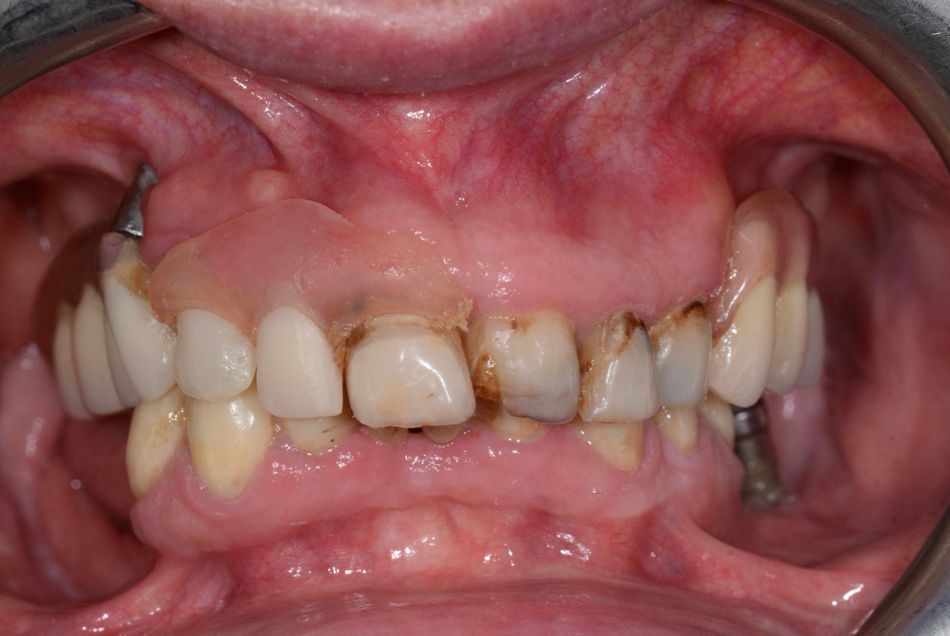

The patient was a 70-year-old woman who presented with the chief complaint of wanting to restore her ability to smile and chew comfortably. Her main expectation focused on improving esthetics, as she had expressed dissatisfaction with her dental appearance and wished to regain a natural, confident smile. She reported no systemic risk factors, was classified as ASA I, and was a non-smoker (Figs. 1,2).

Her dental history included multiple extractions, misplaced implants, and dental decay. Clinically, she demonstrated good plaque control and minimal soft tissue inflammation, although several remaining roots were present in both the upper and lower jaws. In the maxilla, the patient presented with an implant-supported removable prosthesis, and in the mandible, a fixed bridge, both of which were in poor condition (Fig. 3).

After removing the upper jaw prostheses and the lower jaw bridge, the remaining teeth were found to be compromised. Some malpositioned implants were displayed in both arches (Figs. 4-8).

The prognosis of the remaining teeth was unfavorable due to compromised roots and decay. According to the ITI SAC classification, this case was considered complex.